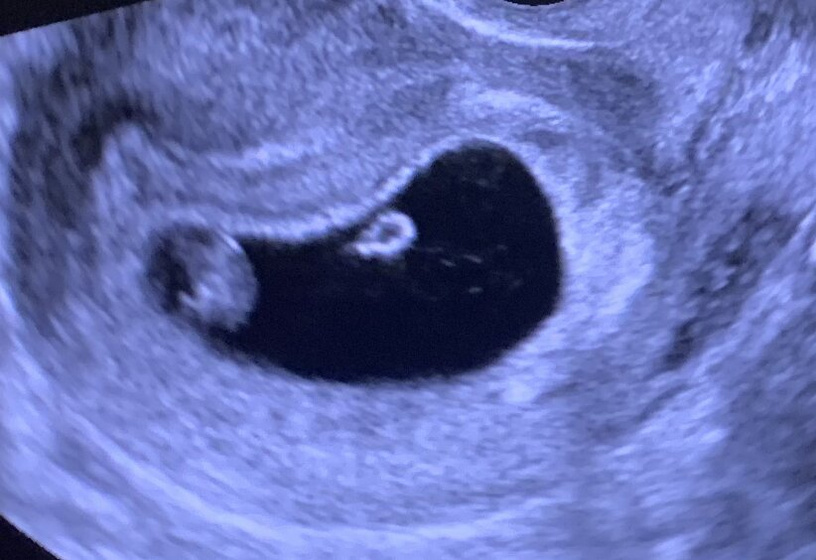

Сходила к репродуктологу и на первое УЗИ ? Сначала глаза закрыла, открыла после слов репродуктолога, что все хорошо ? Утрожестан отменяем, есть своё хорошее ЖТ. ВДПЯ: 35мм, КТР: 11мм, СБ: 148. Срок 7нед.2дня. Я там на кресле вся обмякла, и руки с ногами дрожали, было очень волнительно ? УРА ♥️♥️♥️ Верьте в своих малышей ???

Поздравляю? самая лучшая первая фотография малыша? лёгкой беременности?